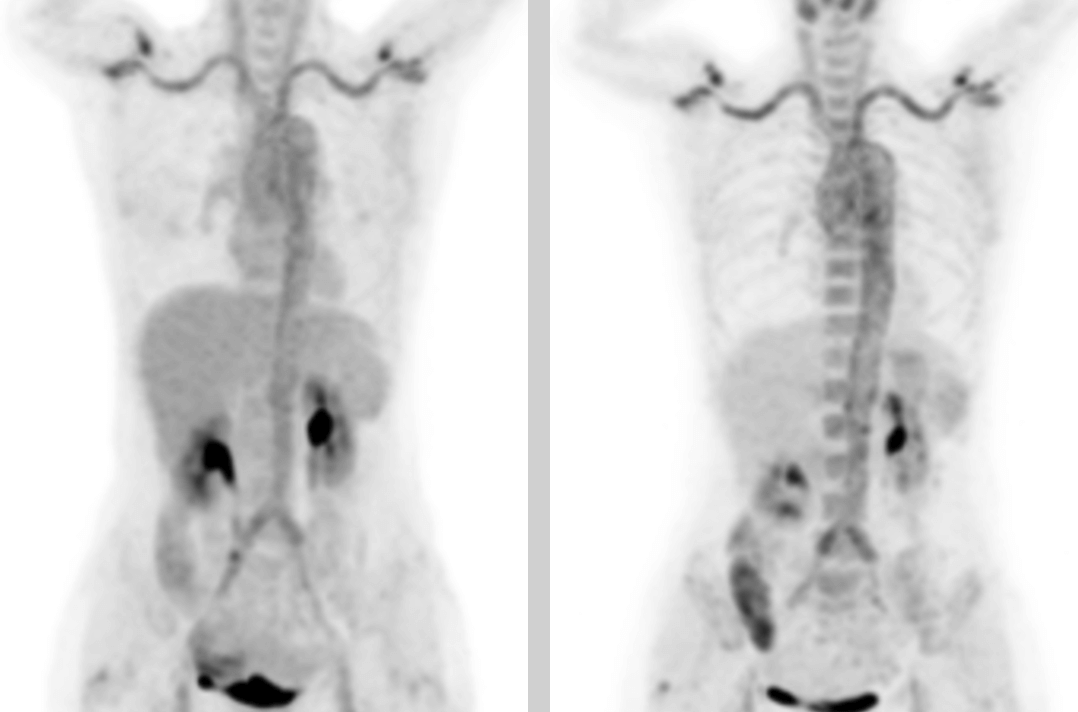

In the PET/CT images, wall thickening with increased glucose metabolism occurred in several parts of the body (bilateral internal carotid artery, common carotid artery, brachiocephalic trunk, bilateral subclavian and axillary arteries, thoracic aorta, abdominal aorta, bilateral common iliac artery, internal iliac artery, external iliac artery and femoral artery), which was considered to be caused by inflammatory changes. Combined with the patient's medical history, clinical symptoms, examination and imaging findings, she was diagnosed with T.A. After standardized anti-inflammation treatment, her body temperature dropped and her condition improved.

This case is a typical example of applying F-FDG PET/CT to the diagnosis of T.A.

F-FDG PET/CT can diagnose T.A. and evaluate disease activity in the active phase. In addition, the whole-body scan can also determine the area of lesions, provide a basis for determining the location of the artery biopsy, and monitor the patient's response after receiving treatment. It can qualitatively indicate increased metabolism of the disease accumulation site. Its semi-quantitative indice SUVmax outperforms serum indices such as ESR and CRP in detecting the sensitivity and specificity of the activity of T.A., which can help improve diagnostic accuracy.